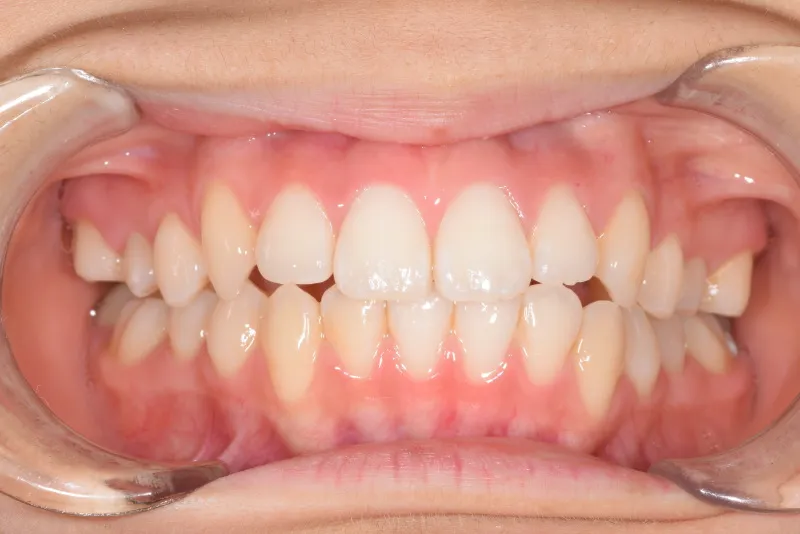

【子供の矯正(一期)】叢生・出っ歯・前歯がゆがんでいる・8才女児【H.M様】

治療終了後

初診時年齢 小学校3年生 (女性) 主訴 出っ歯・前歯がゆがんでいる

診断名 叢生・上顎前突 装置名

出っ歯と前歯のゆがみを主訴に来院されました。

低学年時は取り外しの装置を使用し、高学年になってからは見えにくい固定式の装置を使用して治療しました。

治療回数48回、7年2ヶ月の治療期間で矯正治療を終了しました。

主訴が改善され、ご満足頂きました。